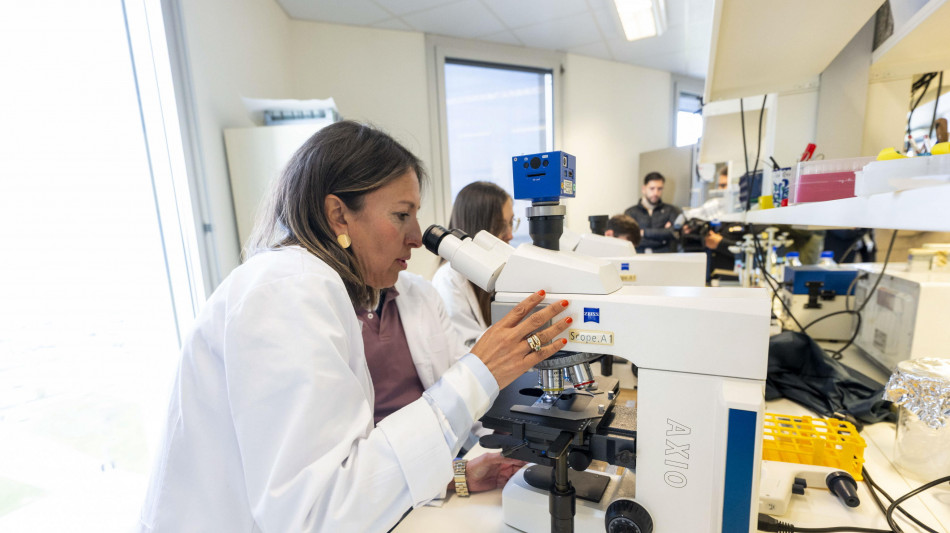

Nuova strategia contro virus Hiv, una puntura per la prevenzione

Collaborazione Sacco-Spallanzani porta in Italia nuovo approccio